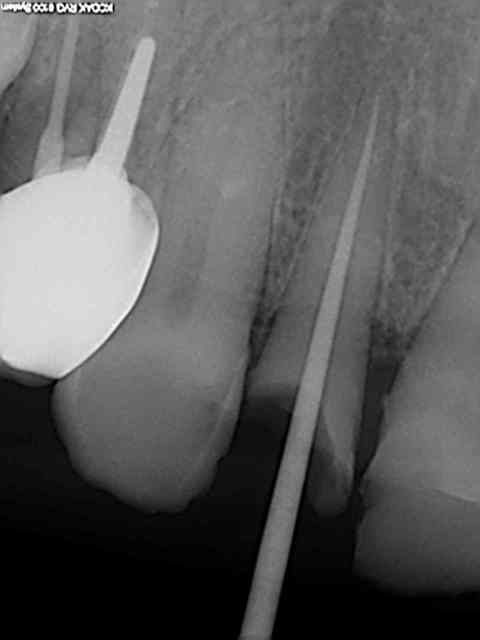

Faut pas pousser. Ce matin patient RDV 11h30 et sorti 12H05, Status radio (on ne sait jamais pas venu depuis 2009) endo, empreinte, provisoire incluses. Un peu énervé par le lapin d'une heure plus tot dans la matinée !

Ouais mais vu la rétraction pulpaire une reconstitution pré endo aurait quelque peu obscurci le champ opératoire, je rase pour y voir plus clair.